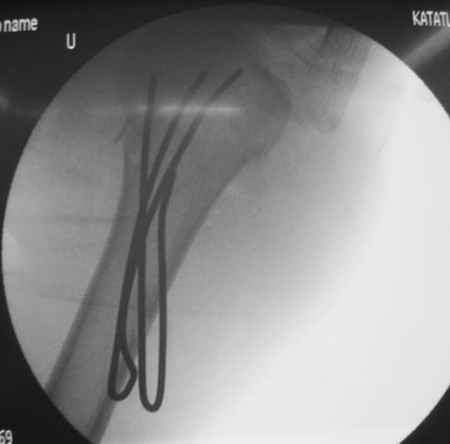

Женя, а как ты водишь спицы, в смысле, как делаешь входное отверстие, и как в него проводишь V-спицу? А то о дна из спиц, та, у которой не дошла до головки одна палочка буквы V, как-то выглядит на рентгенограмме, как будто или через очень большое отверстие введена, или каждая половинка через отдельные отверстия.

Мне кажется, проблема в том, что не все концы спиц зашли в головку, и зашедшие - недостаточно далеко прошли.

Спицы провожу по передней и задней поверхностям плечевой кости через 4,5 мм отверстия на разных уровнях.

Уточни - обе части буквы V вводишь в одно отверстие? А то по снимкам выглядит, что в разные.

V-спица проводится через 4,5 мм отверстие. Видимо, из-за разной длины вторая половина спицы *пролетела* мимо отверстия, что и привело к вторичному смещению костных фрагментов.